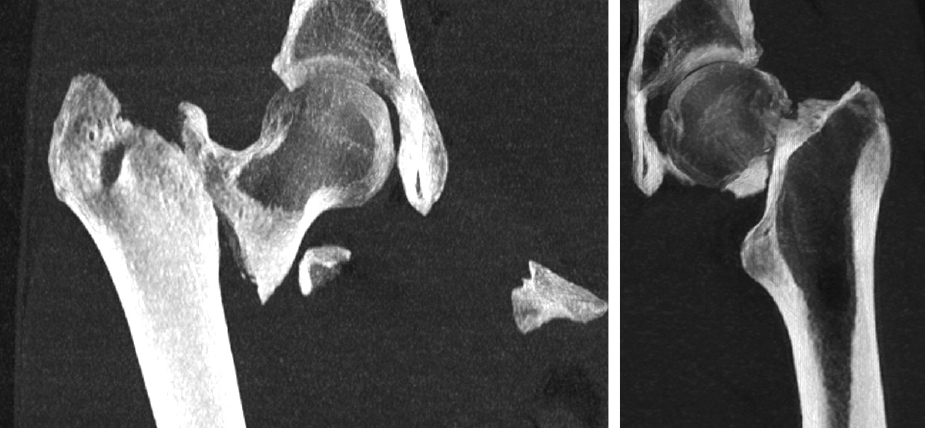

FRACTURA DE PELVIS Y ACETÁBULO

La pelvis conecta la columna con las piernas y soporta el peso del cuerpo. Puede fracturarse por traumatismos graves o por osteoporosis.

El acetábulo es la parte de la pelvis que forma la cavidad donde encaja la cabeza del fémur, formando la articulación de la cadera.

Algunas fracturas sanan con reposo, pero otras necesitan cirugía.

FRACTURA DE CADERA

Las fracturas de cadera (fémur proximal) son frecuentes en personas mayores tras caídas.

La opciones de tratamiento pueden ir desde la osteosíntesis (fijar los huesos con clavos, tornillos o placas) a la prótesis de cadera, dependiendo del tipo de fractura (subcapital, pertrocantérea, subtrocantérea)